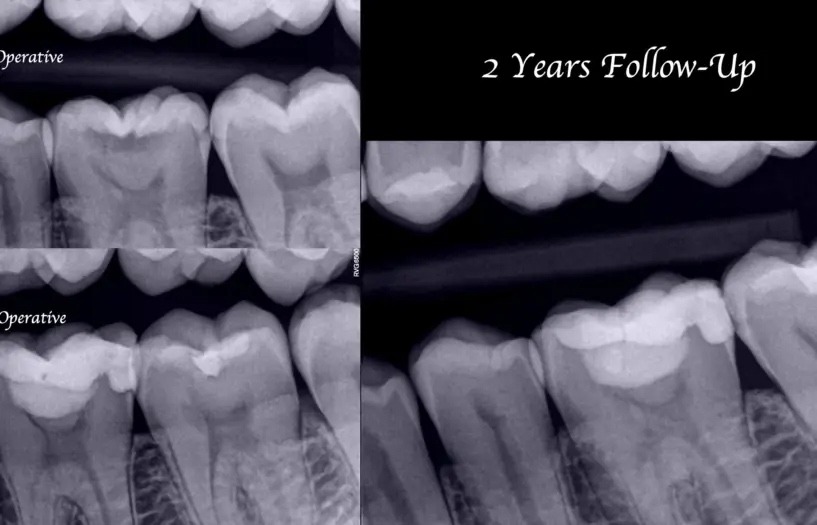

Eines der Hauptmerkmale von Biodentine ist die einfache Handhabung, die hohe Druckfestigkeit und die gute Haftung an der Zahnsubstanz, so dass es als Dentinersatz verwendet werden kann. Aufgrund seiner Eigenschaften lässt es sich leicht in der zu behandelnden Region platzieren und kann als Basis für die endgültige adhäsive koronale Versorgung verwendet werden. Abb. 9 zeigt das Verfahren der vitalen Pulpentherapie. Röntgenologisch kann man bei der Nachuntersuchung nach zwei Jahren eine Retraktion des mesialen Pulpenhorns beobachten. Einer der am meisten geschätzten Vorteile von Biodentine ist, dass es die Zahnhartsubstanz nicht pigmentiert, was es zu einem idealen Material für die Durchführung von Pulpaüberkappungen im Frontzahnbereich macht.

Abb. 9: Vitale Pulpatherapie an Zahn Nr. 19. Bei der Nachuntersuchung nach 2 Jahren ist die Retraktion des mesialen Pulpahorns sichtbar.